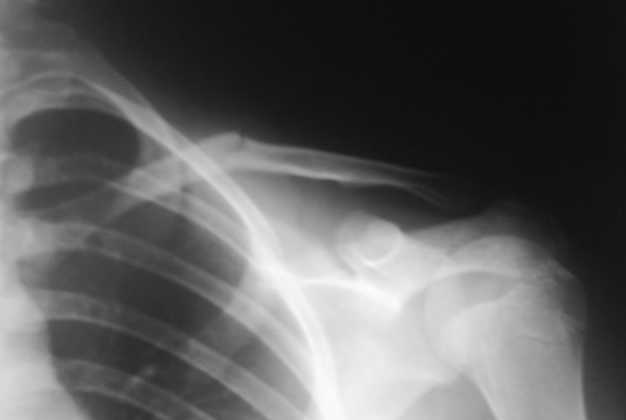

Уважаемые коллеги, травматологи, памятуя о недавней дискуссии о лечении диафизарных переломов ключицы, "Как ключицу не лечи, все равно правильно срастется", поведаю о таком случае.

Девочка 14 лет, на даче упала с турника 05-07-08, в наш травмпункт обратились на следующий день - Диагноз: Закрытый перлом диафиза левой ключицы. Дежурным травматологом наложена 8-образная гипсовая повязка. На следующий день, родители привели девочку с жалобами на давление в левом надплечье и онемение правого предплечья и 1,2, 3-го пальцев кисти.

Мной была немедленно снята наложенная накануне повязка, и заменена на марлевую Дезо. 09-07-го, Дезо заменена на "косыночную" повязку.Сегодня произведен контрольный снимок -На сегодняшний день сохраняется онемение 1-3 пальцев.